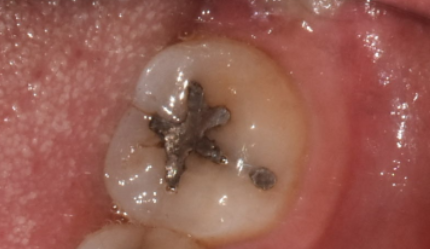

- 이제는 역사속으로... 아말감

240214

이제는 사용하지 않기에 말씀을 안드리려다

여전히 많은 환자분들 입안에서 볼 수 있는 은니 색깔 이것..!

예전에 강동구 치과에서도 많이 사용했던..

레진 대신에 보험 적용이 가능한 아말감 치료

똑같이 치아 땜질 치료이지만

떼운 주변으로 벌어져 충치가 또 생기거나

수은이 나와 몸에 유해해요~

그래서 이제는 잘 사용하지 않는데요.

환자분들께서 예전 기억으로 가끔 찾으셔서

준비해보았습니다.